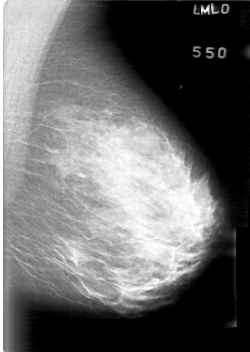

D_4022_1.LEFT_MLO

LEFT_MLO LINES 5266 PIXELS_PER_LINE 3736 BITS_PER_PIXEL 12 RESOLUTION 43.5 NON_OVERLAY